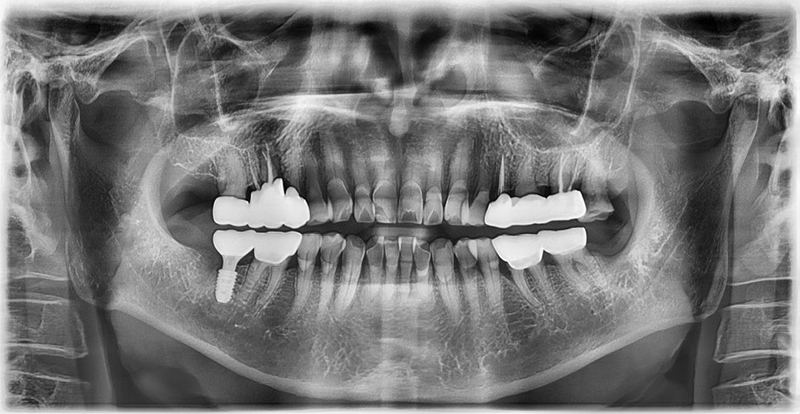

Case 2: 81-year-old male, hypertension

This patient visited us complaining of pain and sensitivity in his lower right molar. He had a history of hypertension and was taking daily medication.

Bleeding control during extraction was stable, so after consulting his physician, we proceeded with implant surgery without stopping his blood pressure medication.

He experienced no pain or bleeding issues after the procedure and was highly satisfied with the outcome.

Three months later, the implant prosthesis was placed successfully.